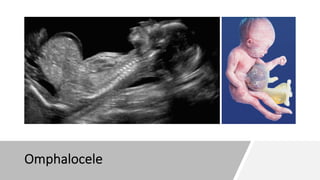

ØOmphalocele

Omphalocele

A small omphalocele (herniation of viscera

into umbilical cord) can be seen.